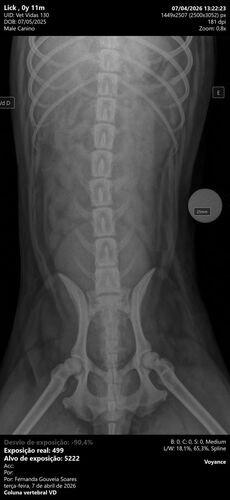

Ontem, nosso cachorro Lucky sofreu um atropelamento e precisou ser levado com urgência ao veterinário. Foi um momento muito difícil e inesperado, e agora ele está em tratamento, lutando para se recuperar 🏥💔

Os custos com atendimento, exames e cuidados já chegaram ao valor de R$ 6.150,00 , e infelizmente não consiguimos arcar com tudo sozinhos neste momento.